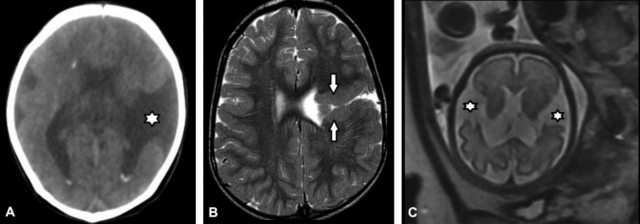

Es el defecto congénito en el que se forman hendiduras en la corteza cerebral.26,27,28 Se las divide en labio abierto o cerrado según la proximidad de sus labios separados por LCR26 (►Fig. 20). En la sustancia gris de los bordes (labios) de las hendiduras o en su vecindad existen capas de polimicrogiria.26,27,28 Pueden ser uni o bilaterales siendo frecuentemente afectados los lóbulos frontales y parietales.26,28 La TC valora las hendiduras lineales de la corteza pero con menor sensibilidad que la RM, siendo éste el método de elección.26,28 La ecografía o RM prenatal pueden diagnosticarla precozmente en los casos de esquisencefalia a labio abierto.26,27,28 Los diagnósticos diferenciales son27,28:

(A-C) TC de cerebro, corte axial (A) en el que se observa esquisencefalia a labio abierto temporal izquierda (*). RM de cerebro, corte axial en ponderación T2 (B). Se pone de manifiesto esquisencefalia a labio cerrado fronto-temporal izquierda; nótese polimicrogiria en sus labios (flechas). La RM fetal, corte axial en ponderación T2 de cerebro (C) muestra esquisencefalia a labio abierto bilateral (*).